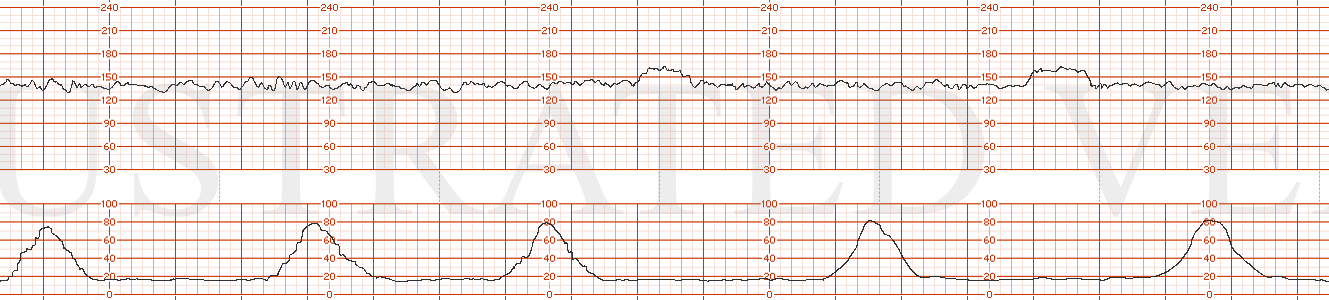

STRIP 22

1. The fhrt is as follows: (baseline hr 150 bpm, normal variability, one acceleration. 1 classic late deceleration is seen in a series of 5 contractions occurring over a 10 minute window. (the late decelerations are too deep (some are nadiring at 50-60 bpm below baseline. Normal lates are more subtle usually 10-30 bpm at most below baseline)